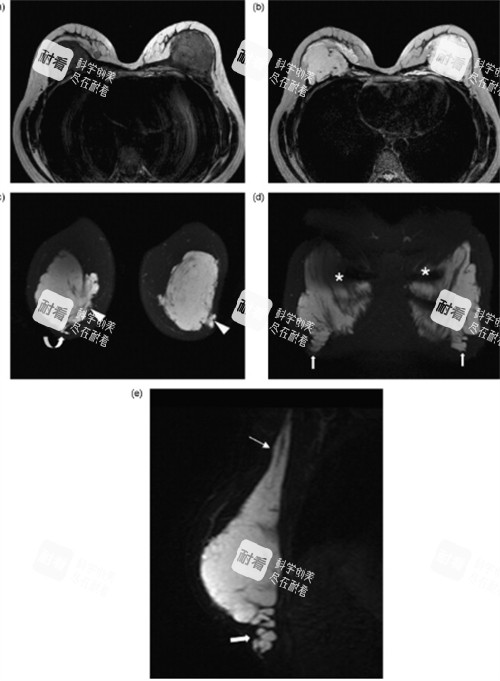

精密可视化操作:采用靠前的 “3D内窥镜结合超声引导” 技术。内窥镜能将手术视野高清放大,让医生在屏幕上清晰分辨奥美定与正常组织;超声则能精密定位深层、隐匿的注射物,实现“指哪打哪”的精密清除。

分层清奥与组织保护:技术核心在于 “分层取出” 。奥美定在体内常呈“树根状”或“蜂窝状”扩散,杨医生通过精细操作,逐层分离、剥离,在较高的效率清除异物的同时,较大程度地保护了血管、神经及健康的乳腺组织与脂肪组织。

术前精密检查:高分辨率MRI(磁共振)检查,这是精密判断奥美定分布范围、层次与毗邻关系的金标准。